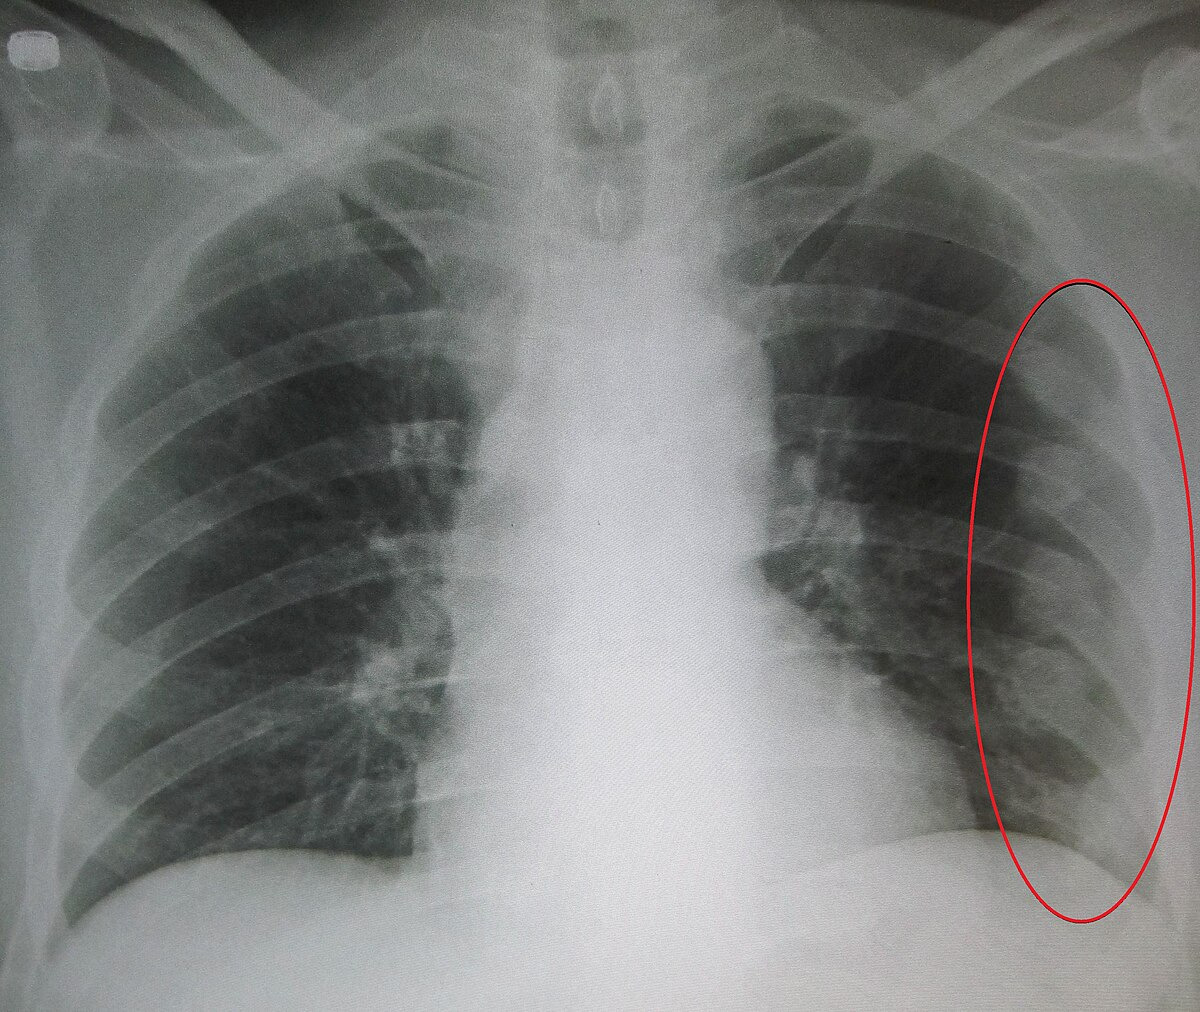

갈비뼈 손상은 넘어지거나 부딪히는 외상 뒤에 생기는 경우가 흔하지만, 강한 기침이 오래 이어졌거나 골다공증이 있는 경우에는 상대적으로 약한 충격에도 골절이 발생할 수 있습니다. 젊고 건강한 사람은 단순 타박상으로 지나가는 경우가 많지만, 고령자나 기저질환이 있는 경우에는 같은 손상이라도 통증이 더 길게 가고 폐 손상 같은 합병증 가능성을 더 주의해서 봐야 합니다. 갈비뼈는 폐와 가까이 있어 골절 양상에 따라 기흉, 혈흉, 폐 손상 등 중증 합병증이 동반될 수 있으므로, 단순히 “숨 쉴 때 좀 아픈 정도”라고 넘기지 말고 갈비뼈 금간 증상의 강도와 변화 양상을 관찰해야 합니다.

한편 갈비뼈 금간 증상과 헷갈리기 쉬운 것이 갈비뼈 타박상, 늑연골염, 흉벽 근육통입니다. 이들 역시 숨을 들이쉴 때 통증이 생길 수 있지만, 외상 직후의 국소 압통이 뚜렷하고 특정 부위를 눌렀을 때 통증이 명확히 재현된다면 골절 가능성을 좀 더 생각하게 됩니다. 다만 실제 진료 현장에서는 단순 갈비뼈 골절과 멍, 흉벽 손상이 치료 방향이 비슷한 경우도 많아 엑스레이를 모든 경우에 바로 찍지 않는 곳도 있습니다. 왜냐하면 치료의 중심이 통증 조절과 호흡 관리에 있기 때문입니다. 다만 숨이 차거나 흉통이 심해지거나, 기침 시 피가 섞이거나, 고열과 누런 가래가 동반되면 상황이 달라집니다. 이 경우는 단순 통증이 아니라 폐 손상이나 감염 가능성까지 확인해야 합니다.

이런 경우는 단순 갈비뼈 금간 증상이 아니라 기흉, 혈흉, 폐 타박상, 폐렴 같은 문제를 배제해야 합니다. 특히 상부 갈비뼈나 다발성 골절은 주변 혈관과 폐에 영향을 줄 가능성이 더 있어 더욱 신중한 접근이 필요합니다.

갈비뼈 금간 증상이 있다고 해서 모두 CT를 찍는 것은 아닙니다. 진료에서는 손상 경위, 통증 위치, 압통 유무, 호흡 상태, 산소포화도, 흉부 청진 등을 먼저 확인합니다. 단순 골절 의심이며 호흡 상태가 안정적이면 엑스레이 없이 보존적 치료를 시작하는 경우도 있습니다. 반면 외상이 크거나, 숨이 차거나, 폐 손상이 의심되거나, 다발성 골절 가능성이 있으면 영상검사가 더 적극적으로 진행될 수 있습니다. 즉, 검사 여부는 “뼈가 정말 금이 갔는지”만 확인하기 위한 목적보다, 위험한 합병증이 숨어 있는지를 판단하기 위해 결정되는 경우가 많습니다.